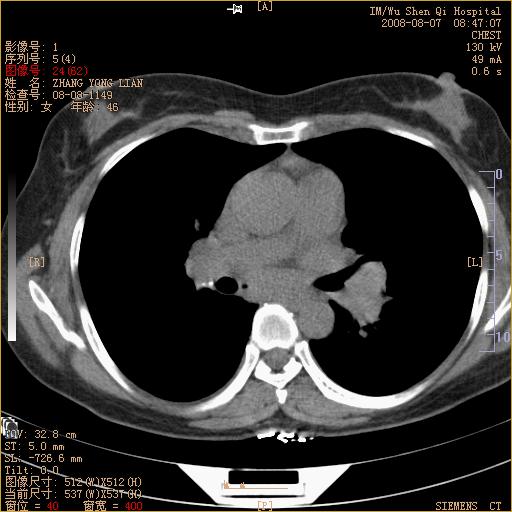

标题: CT15050:女,46岁,咳嗽胸痛一月余 [打印本页]

纵隔窗没发全,左下肺近胸膜处结节。有长毛刺,纵隔淋巴结增大,不排除恶性病变。

考虑肺癌

考虑左肺下叶后基底段周围型肺癌伴纵隔淋巴结转移可能性大。

左下肺ca并纵隔及左肺门区淋巴结转移。

脾脏低密度结节转移不排除。

1)考虑左肺下叶后基底段周围型肺癌伴纵隔淋巴结转移。2)脾内低密度灶,性质待定;不排除转移瘤可能。